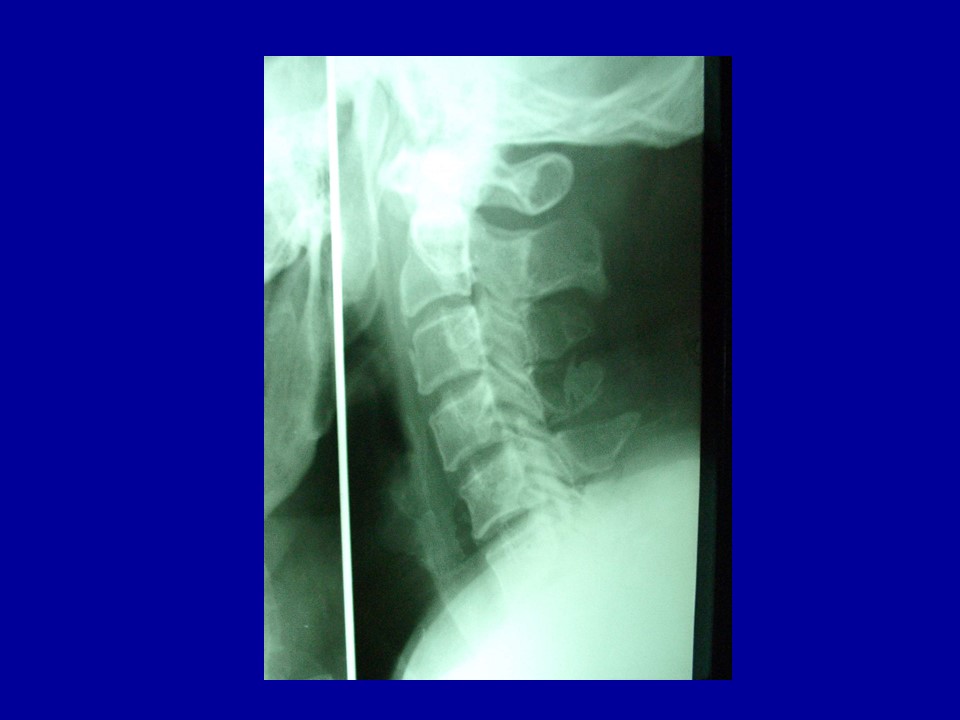

颈椎病的解剖及分型治疗PPT